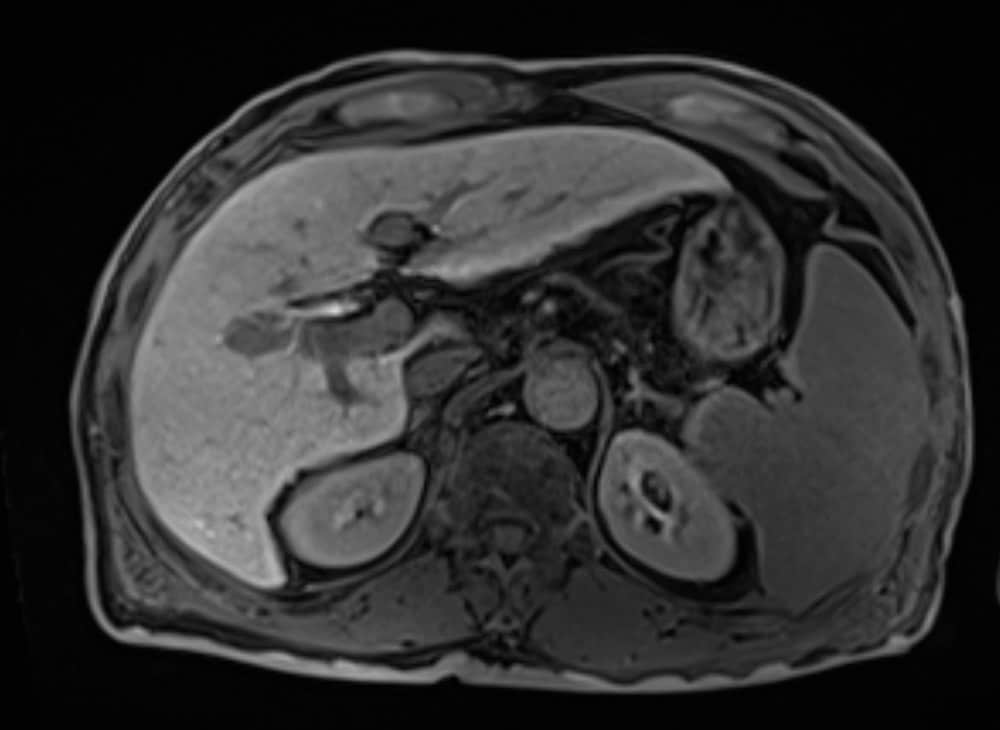

60歳代、男性、57kg、肝細胞癌

前医よりB型慢性肝炎に対して核酸アナログ投与し定期フォローを継続されていた.AFP上昇,腹部USでの画像異常を指摘され精査加療目的に当院紹介受診となり,EOB-MRIを施行した.

EOB-MRIの結果から門脈本幹までの腫瘍栓を伴う肝細胞癌と診断した.EOB-MRI肝細胞相で不均一高信号を呈する病変ではなく,均一低信号を呈しており複合免疫療法が奏効する可能性があると考えられた.Vp4の門脈腫瘍栓を伴う切除不能進行肝癌に対し複合免疫療法(Atezolizumab/Bevacizumab併用療法)を開始した.4コース終了後には門脈腫瘍栓一部残存を認めるも肝腫瘤は著明に縮小し,5コース終了後に根治切除術(肝右葉切除術+門脈血栓除去術)を施行した.術後は薬物療法の再開なく現在までの約14ヶ月無再発で経過観察継続中である.

EOB-MRIで門脈腫瘍栓を伴う肝細胞癌であること,不均一高信号を呈する病変で無いことを確認し複合免疫療法(Atezolizumab/Bevacizumab併用療法)を開始した.EOB-MRI肝細胞相は肝細胞癌におけるWnt/βカテニン変異のイメージングバイオマーカーとなることが知られており(Ueno A et al. J Hepatol 61:1080-1087,2014),不均一高信号な病変は複合免疫療法の治療効果が乏しい可能性が指摘されている(Sasaki et al. Cancers,14,827,2022).必ずしも治療奏効を保障するものでは無いが,本症例では肝細胞相で均一低信号を呈しており,複合免疫療法の治療効果が期待される症例であった.